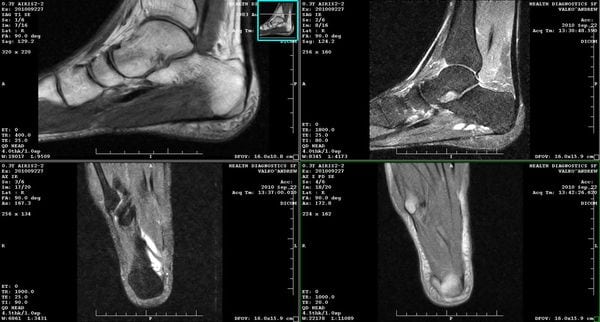

Визуализирующие возможности МРТ голеностопного сустава и стопы

Магнитно-резонансная томография – это современный метод исследования, позволяющий визуализировать патологические изменения в связках, мышцах, сухожилиях, нервах, сосудах и суставах стопы. Исследование проводят в сложных диагностических ситуациях, когда врачам не удается выявить причину болей другими методами. МРТ стопы позволяет обнаружить практически любые дефекты в тканях на самых ранних стадиях.

Магнитно-резонансная томография позволяет получить трехмерное послойное изображение мягких тканей. На томограммах отлично визуализируются все структуры суставов стопы, связки, мышечные сухожилия, нервы и сосуды. Однако МРТ малоинформативна в диагностике заболеваний костей. С этой целью врачи обычно используют компьютерную томографию (КТ).